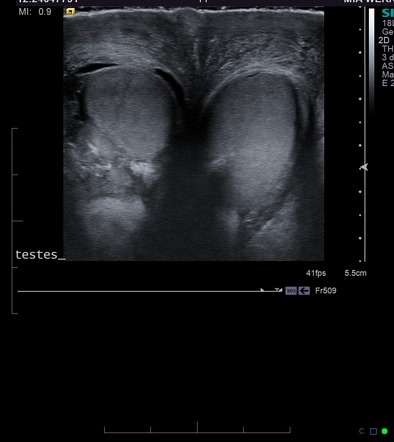

Diagnosis

Doctors may recommend:

These tests help identify the exact cause.